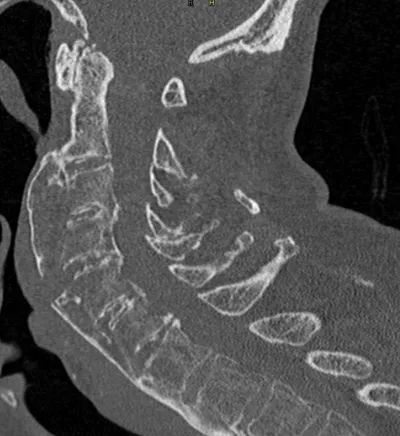

Ankylosis Radiology Images

This collection contains 1 radiology images related to ankylosis, including various imaging modalities such as X-rays, MRIs, CT scans, and ultrasound images commonly used in medical diagnosis and education.